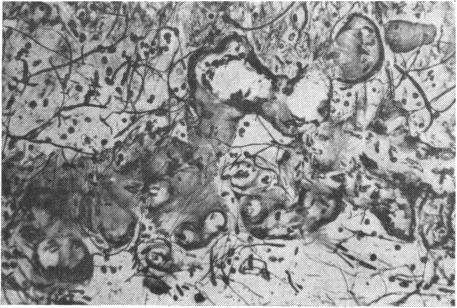

RETINAL PATHOLOGY AFTER CENTRAL RETINAL VEIN OCCLUSION.

Br J Ophthalmol. 1961 Oct;45(10):683-94. doi: 10.1136/bjo.45.10.683.